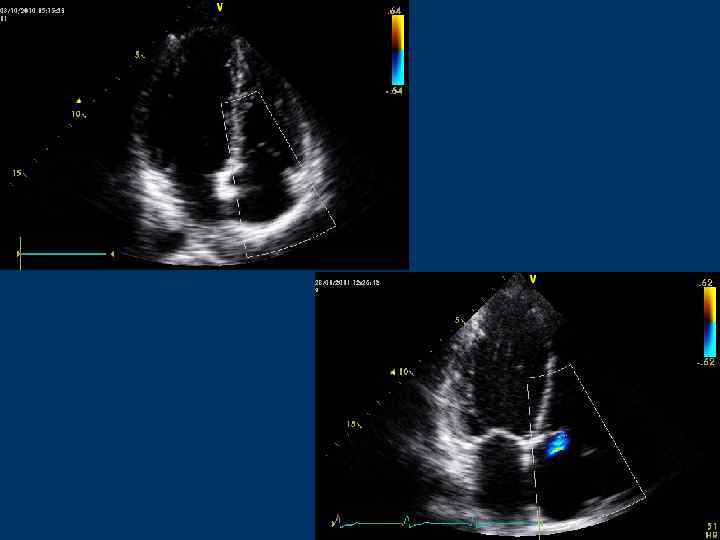

Транстрикуспидальный диастолический поток • Парастернальная позиция по короткой оси ЛЖ на уровне основания сердца • Позиция длинной оси ПЖ • Апикальная 4 -камерная позиция • Апикальная 5 -камерная позиция • Субксифоидальная позиция

Транстрикуспидальный поток

Транстрикуспидальный диастолический поток Контрольный объем располагают над створками ТК или в области правого фиброзного АВ кольца

Транстрикуспидальный поток Скорость пика Е – 0, 5 м/с (0, 3 -0, 7 )